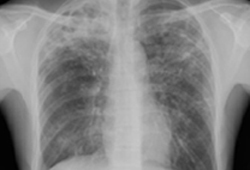

Portable chest x-ray with bibasilar opacities, worse on the right than the left, in a patient with hospital-acquired pneumonia

From the personal collection of Dr F.W. Arnold, Division of Infectious Diseases, Department of Medicine, University of Louisville School of Medicine